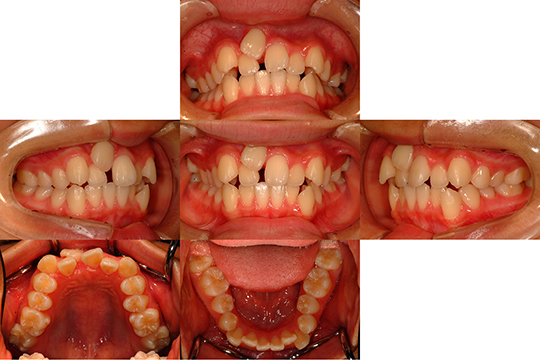

| 主訴 | 上の乳歯(上顎右側乳中切歯)が残っている |

| 初診時年齢 | 12才10か月 |

| 診断名 | 上下顎叢生を伴う上顎右側中切歯萌出遅延 |

| 使用装置 | 上下顎マルチブラケット装置 |

| 抜歯or非抜歯 | 抜歯 |

| 抜歯部位 | 上顎右側:乳中切歯、第一小臼歯 |